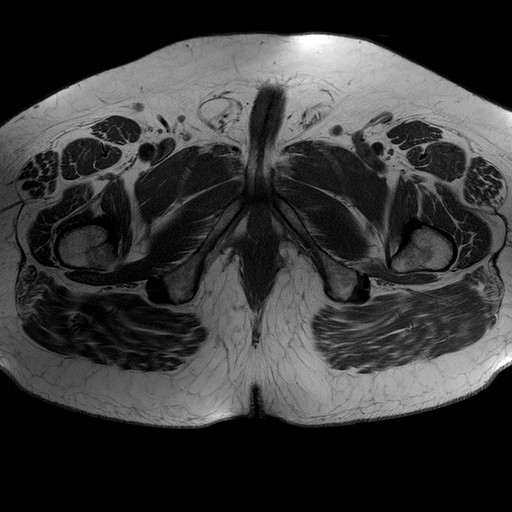

Esami: RMN BACINO

T1W_TSE

Evidenti e simmetriche alterazioni osteofitosiche in regione coxo femorale con riduzione delle rime articolari. Degenerazione completa del cercine glenoideo. Non attuali segni di versamento articolare. Non segni di edema osseo che escludono attuale algodistrofia od osteonecrosi. Lieve e simmetrica riduzione del trofismo della muscolatura glutea.